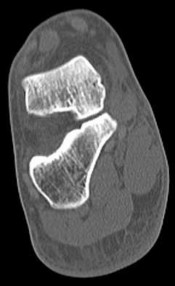

Figures 3a through 3h

1

Normal foot

2

Calcaneonavicular (CN) coalition

3

Talocalcaneal (TC) middle facet coalition

4

TC posterior facet coalition

- TC posterior facet coalition

Figure 3a shows a flatfoot. Figure 3b shows an MF and TB, but not a C sign. Figure 3c shows a bony irregularity between the calcaneus and the navicular and a WN. Figure 3d shows an MF. Figure 3e shows an MF, but narrowing or loss of the posterior facet. Figures 3f through 3h show medial edema and joint irregularities consistent with a posterior facet coalition.